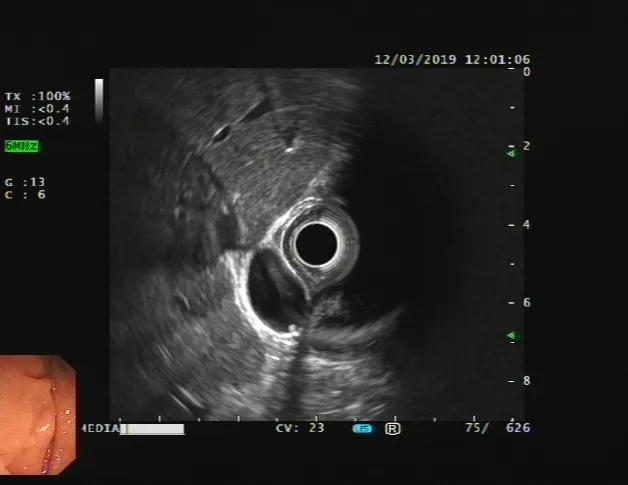

比如我们发现了十二指肠一个粘膜下隆起(下图),但是无法判断他的性质。

通过超声内镜,我们可以看出它在哪一层,是什么结构、什么性质。见下图: